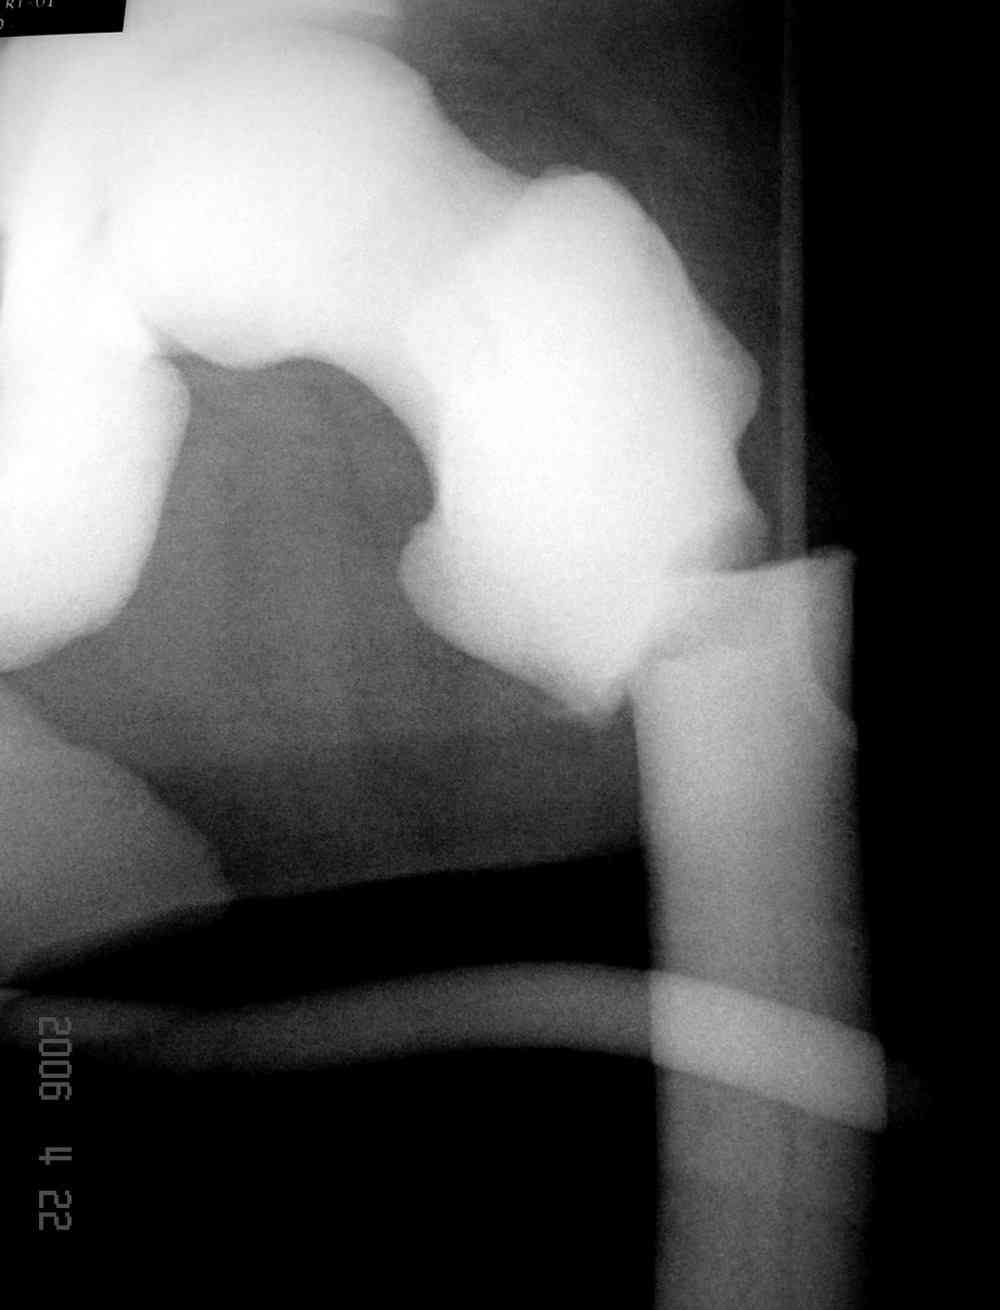

Re: [2/3] Перелом проксимального бедра

Здесь у меня дополнительные снимки с большим разрешением и в разных режимах, а то те дигитал снимки совсем очень блеклые, может, эти изображени изменят выбор тактики